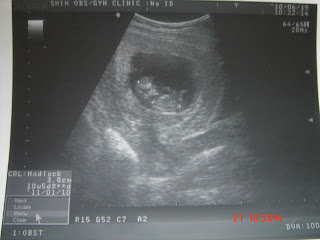

到了那裡,醫生趕快幫我照超音波,BaBe一樣在肚子裡手腳揮舞著

(超極可愛)!!早上沒什麼人,醫生有檢查的比較仔細點又很久,